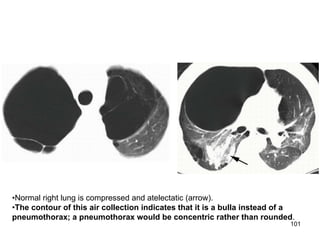

•Normal right lung is compressed and atelectatic (arrow).

•The contour of this air collection indicates that it is a bulla instead of a

pneumothorax; a pneumothorax would be concentric rather than rounded.